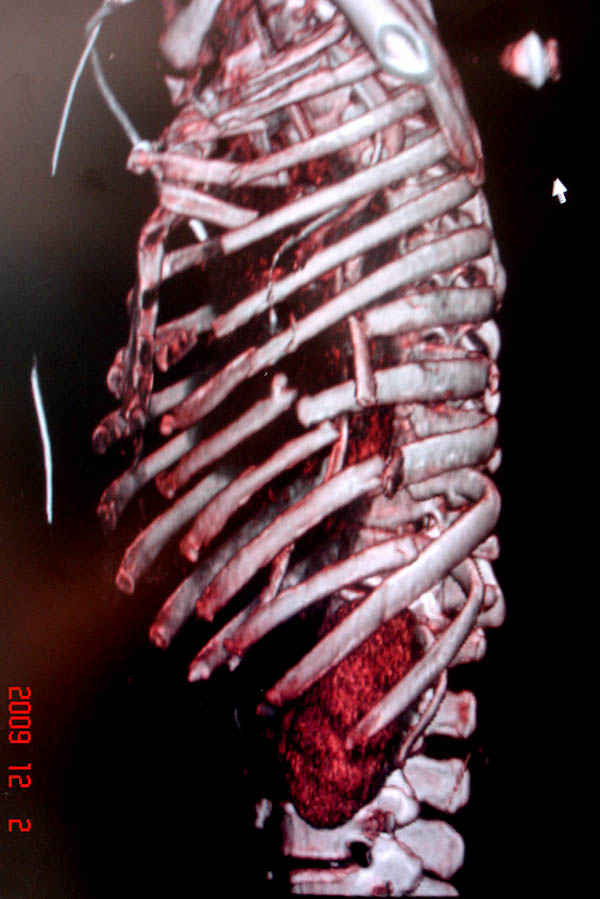

К нам поступила больная 56 лет после автоаварии в бессознательном состоянии, которая срочно заинтубирована в приемном отделении и сделаны необходимые исследования. Данные КТ и рентген показали перелом дистального бедра и Dissociation upper extremity - закрытый отрыв левой верхней конечности на уровне грудинно-ключичного сочленения и множественные переломы ребер.

На седьмые сутки нами совместно с торакальным хирургом сделана операция по фиксации грудинно-ключичного сочленения и переломов ребер.

Не все переломы ребра фиксированы, и поэтому хотели услышать комментарии тех, у кого имеется опыт.

В основном переломы ребер мы тоже не фиксируем, но учитывая, что в данной презентации, кроме разрыва грудинно-ключичного сочленения, дополнительно имелись множественные переломы ребер, некоторые сегментарные. После такой травмы трудно восстановить функцию западающей грудной клетки, и поэтому после дисскуссии с торакальным хирургом мы коллективно приняли решение зафиксировать переломы ребер тоже.

Отмеченный Александром случай из России заинтриговал меня давно и как раз выдался случай..., тем более новый имплант от Synthesа в 1.5 мм отвечал всем требованиям остеосинтеза ребер.